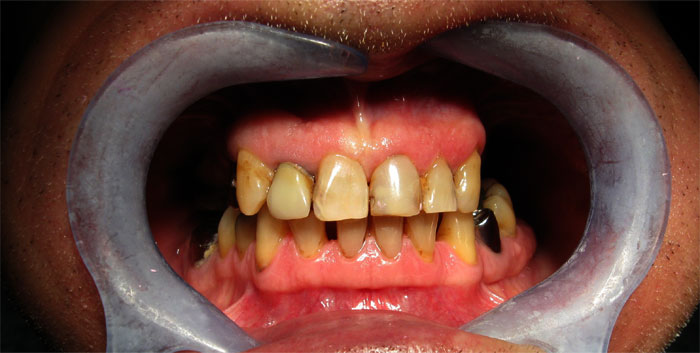

CAS N°1 Bridges et couronnes sur implant dentaire DIO et sur dents naturelles. Réhabilitation complète mâchoire supérieure, détartrage et blanchiment mâchoire inférieure.

Europa Dental Hongrie